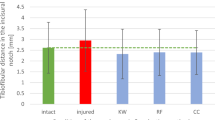

The results are shown as mean values and 95% confidence intervals as error bars for visual comparison. This means that samples with non-overlapping error bars are significantly different, with p ≤ 0.05.

The HT showed an overall larger mean diastasis with 1.5 ± 0.8 mm, compared to the STT with 1.2 ± 1.2 mm (p = 0.047), regardless of the applied force, the instability level, or the direction of the induced instability. The diastasis measured with the STT ranged from 0.5 ± 0.2 mm to 3.0 ± 1.6 mm depending on the instability level, while the range with the HT was 1.1 ± 0.4 mm to 2.3 ± 1.0 mm (Fig. 3, Table 3).

Level of instability and applied forces (in color) with the corresponding diastasis in (A) for the syndesmosis-test-tool (STT) and in (B) for the Hook-Test (HT). In (C), the comparison of the diastasis for the syndesmosis-test-tool (STT) and the hook-test (HT) regardless of the force, is shown. Solid horizontal line: instability threshold of 2 mm. The diastases are given as mean ± 0.95 confidence interval as error bars (n = 20). Samples with non-overlapping error bars differ significantly, with p ≤ 0.05.

By comparing both devices for each instability level, the HT showed significantly greater diastasis in each instability level (level 1 p < 0.001, level 2 p = 0.003, level 3 p = 0.003, level 4 p = 0.002, Table 3) compared to the STT, except at the maximal instability (instability level 5, p = 0.101, Table 3). The pairwise comparisons of the diastases between both devices for each instability level are given in Table 3.

Both devices showed different slopes depending on the instability level, which is statistically given as an interaction between the device and instability level with p = 0.003 in Table 2. This means, that HT and STT produced different diastases depending on the instability level. However, statistical analysis revealed a very comparable frequency of reaching significance for both devices, except that the STT showed significance between native condition (level 1) and instability level 3 (p < 0.001), in contrast to the HT (p = 0.140, Table 4). With a moderate effect (Cohen's d greater 0.5) that distinguishes between different instability levels, the effect sizes for STT are larger compared to HT (Table 4). The greater the effect size, the greater the difference in diastasis between the two instability levels.

For visual comparison, Fig. 3C displays the diastasis of both devices in dependency on the instability level. The largest increase in diastasis between adjacent instability levels produced the STT from instability levels 4 to 5 with 2.0 ± 1.7 mm (p < 0.001). For the HT, the increase from instability level 4 to 5 of 0.7 ± 0.7 mm was also the greatest between adjacent instability levels within the HT (p = 0.001) but was almost three times smaller compared to the STT. The difference between native condition (level 1) and maximal instability (level 5) was 2.5 ± 1.5 mm for the STT and 1.1 ± 0.8 mm for the HT.

The effect sizes showed better discrimination between instability levels for the STT, than for the HT.

Visually discriminating in diastasis between the different instability levels is quite hard, despite its significance.